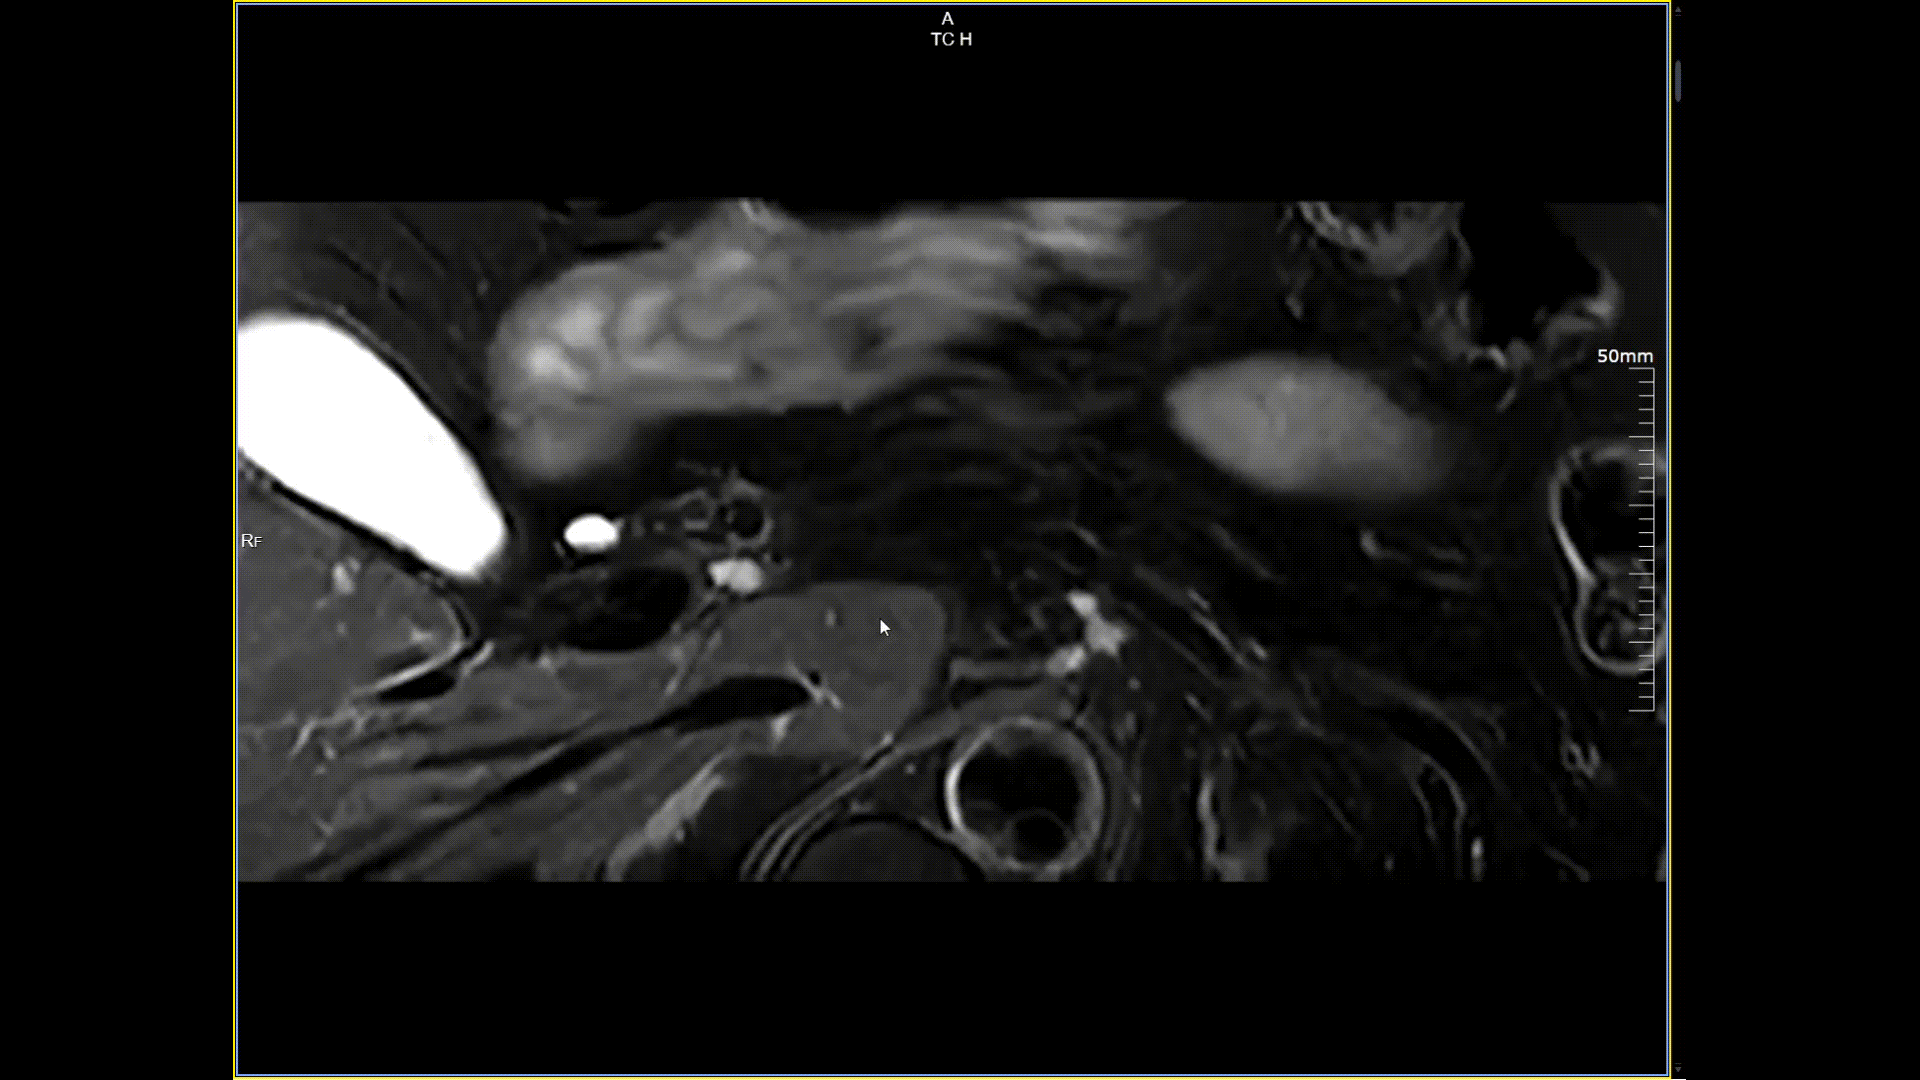

胰腺小视野高分辨,分辨率0.5*0.5mm